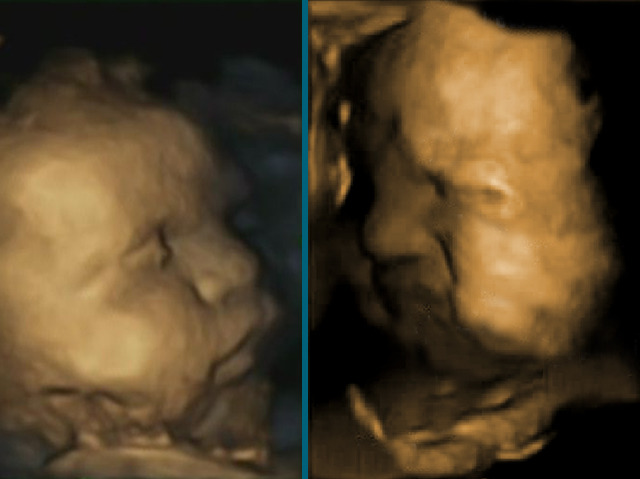

Baby Faces

As adults it’s hard to resist pulling faces at babies to see their reaction. Perhaps surprisingly babies have been practicing pulling faces for weeks before they are even born. A recent study shows that between 24 and 36 weeks gestation healthy infants make spontaneous facial expressions, increasing in complexity and co-ordination as they develop. In the ultrasound scan above, the 32-week infant on the right pulls a distress-like expression. However, it‘s not known if the expressions relate to emotional responses as they will in later life, or are perhaps just the body trialling the use and co-ordination of certain muscles. Knowing more about how facial expressions develop in foetuses could provide early warning of abnormal development or unhealthy in utero conditions.